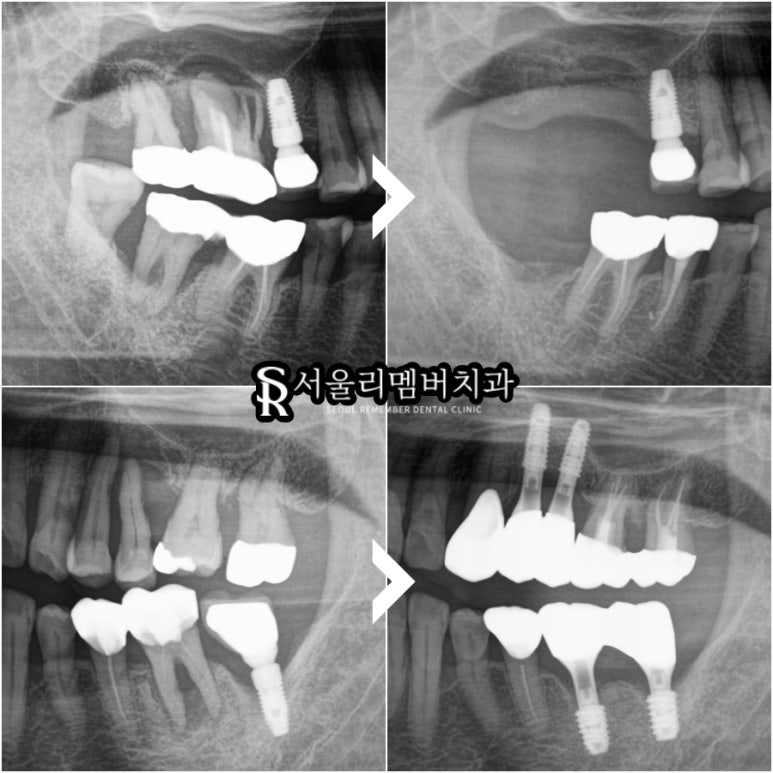

boneloss가 심한 부위부터

발치를 하고 염증 조직을 긁어내는 과정을

시작했습니다.

내부에 감염된 육아조직이 남아있지 않도록

깨끗하게 청소해 주면

인간의 치유력으로

어느 정도 신생골이 차오르니 말이죠.

또한 상대적으로 뼈가 덜 녹은 부위는

임플란트를 심어서

어금니를 회복시켜주기로 했는데요,

2024.09.27 ~ 2025.08.14

골소실이 매우 심각했던

오른쪽 위아래 어금니는

현재 발치 후 뼈가 회복되기를

기다려주고 있는 상태이며

2024.09.27 / 2025.08.14

왼쪽은 치료를 모두 마쳤기에

환자는 왼쪽으로 식사하시면 됩니다.

파노라마 엑스레이에서 보면

픽스처 높이까지 잇몸뼈가 잘 치유되어

있는 것을 확인할 수 있습니다.